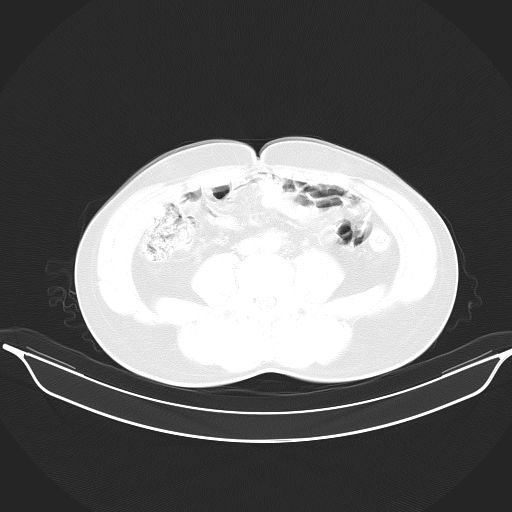

标题: CT25490:男,40岁,体检发现;无其它不适。 [打印本页]

标题: CT25490:男,40岁,体检发现;无其它不适。

考虑右下肺周围性肺癌并肺内多发转移,纵隔淋巴结转移!

支持 !考虑右下肺周围性肺癌并肺内多发转移,纵隔淋巴结转移,(气管前腔静脉后,隆突下,主动脉弓下都有了)

1、均为转移,原发灶不在肺内。2、肺癌肺转移。